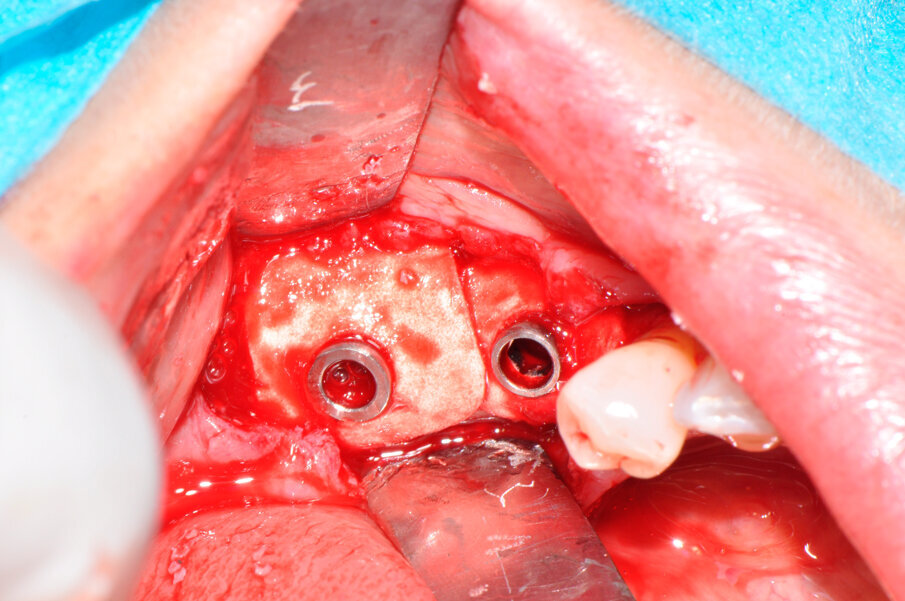

Il caso in esame riguarda una paziente di 53 anni, fumatrice, che si presentava all’osservazione per il consueto controllo periodico lamentando sanguinamento e dolore gengivale durante le manovre di igiene orale a livello di due impianti situati in posizione 4.6 e 4.7. A seguito dell’esecuzione di una CBCT per altri motivi si è potuto evidenziare un marcato riassorbimento osseo perimplantare (Fig. 1). Come si può osservare durante la chirurgia (Fig. 3) l’esposizione della superficie implantare è superiore al 50%. In entrambe le fixture con un maggior coinvolgimento in posizione 4.6. È stata inoltre riscontrata una sofferenza della mucosa attorno ai monconi delle due fixture.

Il ponte cementato e i monconi implantari sono stati rimossi per procedere all’apertura del lembo mucoperiosteo ed esporre totalmente gli impianti e la superficie ossea; l’esame clinico confermava l’entità del riassorbimento osseo già osservata all’esame radiografico (Fig. 3). Una volta rimosso il tessuto granulomatoso sviluppatosi intorno agli impianti (Fig. 4), si è eseguito un debridement perimplantare con conseguente rimozione meccanica delle spire esposte. La superficie dell’impianto è stata ripulita con air polishing, polvere di glicina e lucidatura finale (Fig. 5). Il letto osseo perimplantare è stato cruentato per stimolare l’angiogenesi e l’integrazione con l’innesto. Il granulato, precedentemente idratato, è stato innestato nel difetto osseo a coprire le spire della superficie esposta di entrambi gli impianti fino a ripristinare il profilo osseo originale (Fig. 6).

Fig. 3 - I due difetti perimplantari all’apertura del lembo.

Fig. 6 - I due difetti perimplantari sono innestati col biomateriale a lento riassorbimento.

Fig. 7 - Le membrane in collagene sono posizionate attorno agli impianti dopo averle opportunamente forate.